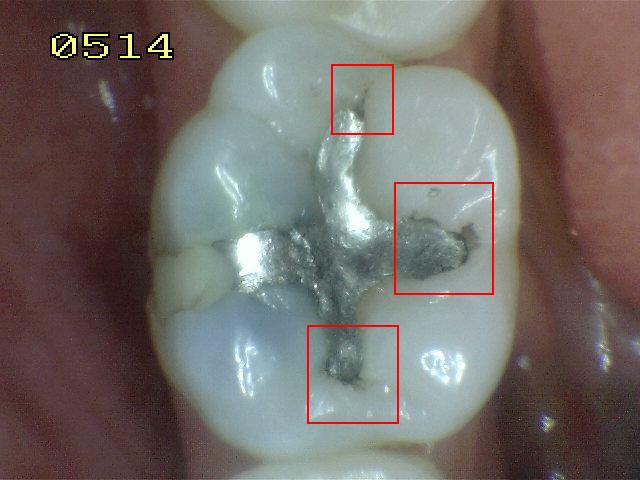

Código 5

(Caries Severa): Cavidad

detectable con dentina visible hasta la mitad de la superficie

-

Cavidad detectable

adyacente a la restauración/sellante con dentina visible

en el espacio de interfase con signos de caries tal como

se describe en el código 4, además de un espacio > 0,5

mm de ancho.

En los casos en que

los márgenes no son visibles, hay evidencia de pérdida

de continuidad en el margen de la restauración/sellante

y en la dentina, detectada por el paso de la punta de

0,5 mm de la sonda cuando se pasa por el margen de la

restauración/sellante.

Criterios para

determinar si la lesión es activa o detenida